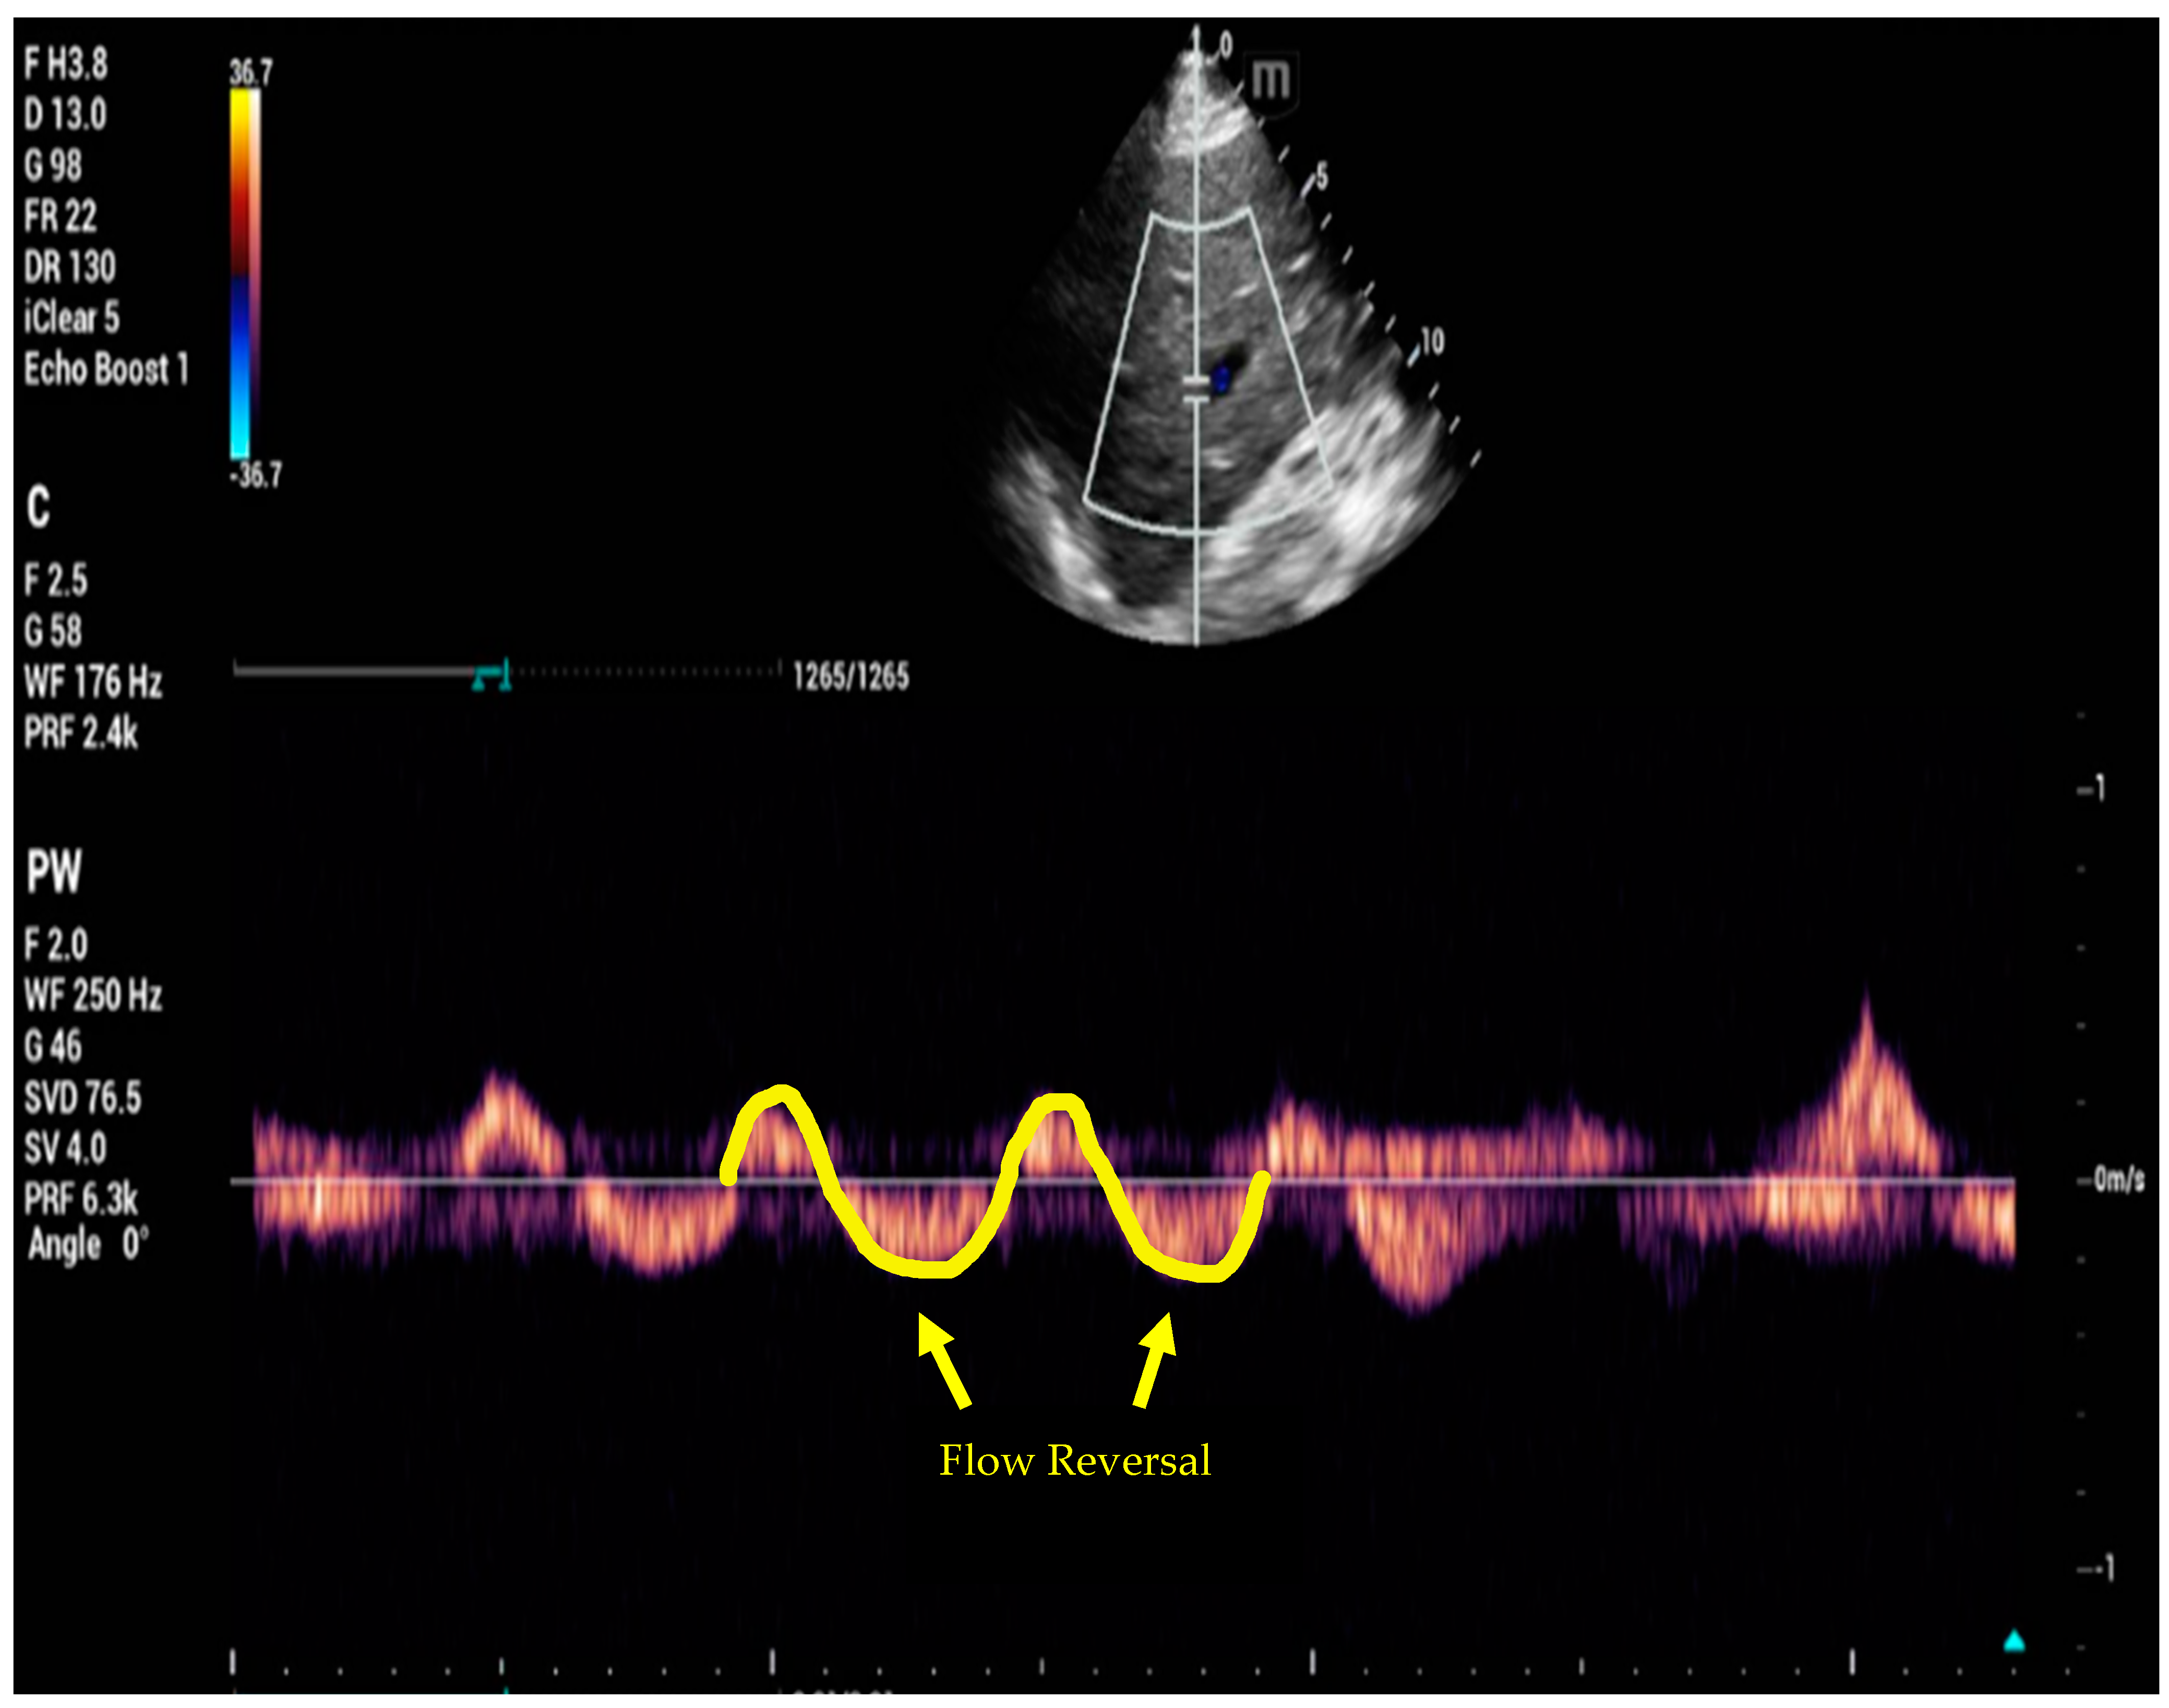

6. Venous Excess Ultrasound Score

- Beaubien-Souligny, W.; Rola, P.; Haycock, K.; Bouchard, J.; Lamarche, Y.; Spiegel, R.; Denault, A.Y. Quantifying systemic congestion with Point-Of-Care ultrasound: Development of the venous excess ultrasound grading system. Ultrasound J. 2020, 12, 16. [Google Scholar] [CrossRef]

- Longino, A.; Martin, K.; Leyba, K.; Siegel, G.; Gill, E.; Douglas, I.S.; Burke, J. Correlation between the VExUS score and right atrial pressure: A pilot prospective observational study. Crit. Care 2023, 27, 205. [Google Scholar] [CrossRef]

- Spiegel, R.; Teeter, W.; Sullivan, S.; Tupchong, K.; Mohammed, N.; Sutherland, M.; Leibner, E.; Rola, P.; Galvagno, S.M.; Jr Murthi, S.B. The use of venous Doppler to predict adverse kidney events in a general ICU cohort. Crit. Care 2020, 24, 615. [Google Scholar] [CrossRef]

- Andrei, S.; Bahr, P.A.; Nguyen, M.; Bouhemad, B.; Guinot, P.G. Prevalence of systemic venous congestion assessed by Venous Excess Ultrasound Grading System (VExUS) and association with acute kidney injury in a general ICU cohort: A prospective multicentric study. Crit. Care 2023, 27, 224. [Google Scholar] [CrossRef]

- Argaiz, E.R.; Rola, P.; Gamba, G. Dynamic Changes in Portal Vein Flow during Decongestion in Patients with Heart Failure and Cardio-Renal Syndrome: A POCUS Case Series. Cardiorenal Med. 2021, 11, 59–66. [Google Scholar] [CrossRef]

- Rola, P.; Miralles-Aguiar, F.; Argaiz, E.; Beaubien-Souligny, W.; Haycock, K.; Karimov, T.; Dinh, V.A.; Spiegel, R. Clinical applications of the venous excess ultrasound (VExUS) score: Conceptual review and case series. Ultrasound J. 2021, 13, 32. [Google Scholar] [CrossRef] [PubMed]